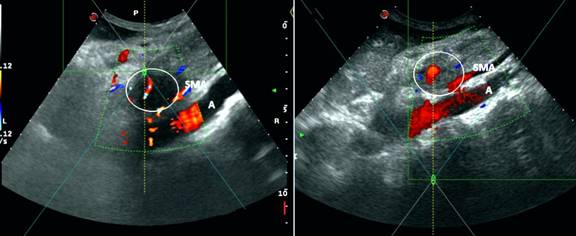

The patient’s answers showed poor (25 points) Global Health Status (GHS) and moderate (50 points) pancreatic pain before treatment. At that time the patient’s BMI was 14.9 kg/m2. The HIFU ablation was performed with Model JC therapeutic system (Chongqing Haifu Medical Technology Co. Ltd., China) under sedation in prone position for 2 hours with 752 seconds real ablation time and mean energy of the beam of 103 W. The first hyper echogenic changes appeared after 150 seconds as ultrasound (US) signs of coagulative necrosis. Immediately after the ablation the hyper echogenic changes were observed in the whole tumor mass (Figure 4). The patient was discharged from the hospital after 4 days in a good general condition with no clinical, laboratory or imaging data of complications. The patient continued the FOLFOX4 treatment for a total of 10 courses before and after HIFU.

Figure 4. Ultrasound image of the hypo-echogenic tumor before HIFU ablation with infiltration of the SMA (on the left side) and the hyper-echogenic changes of the tumor mass immediately after HIFU procedure (on the right side). |